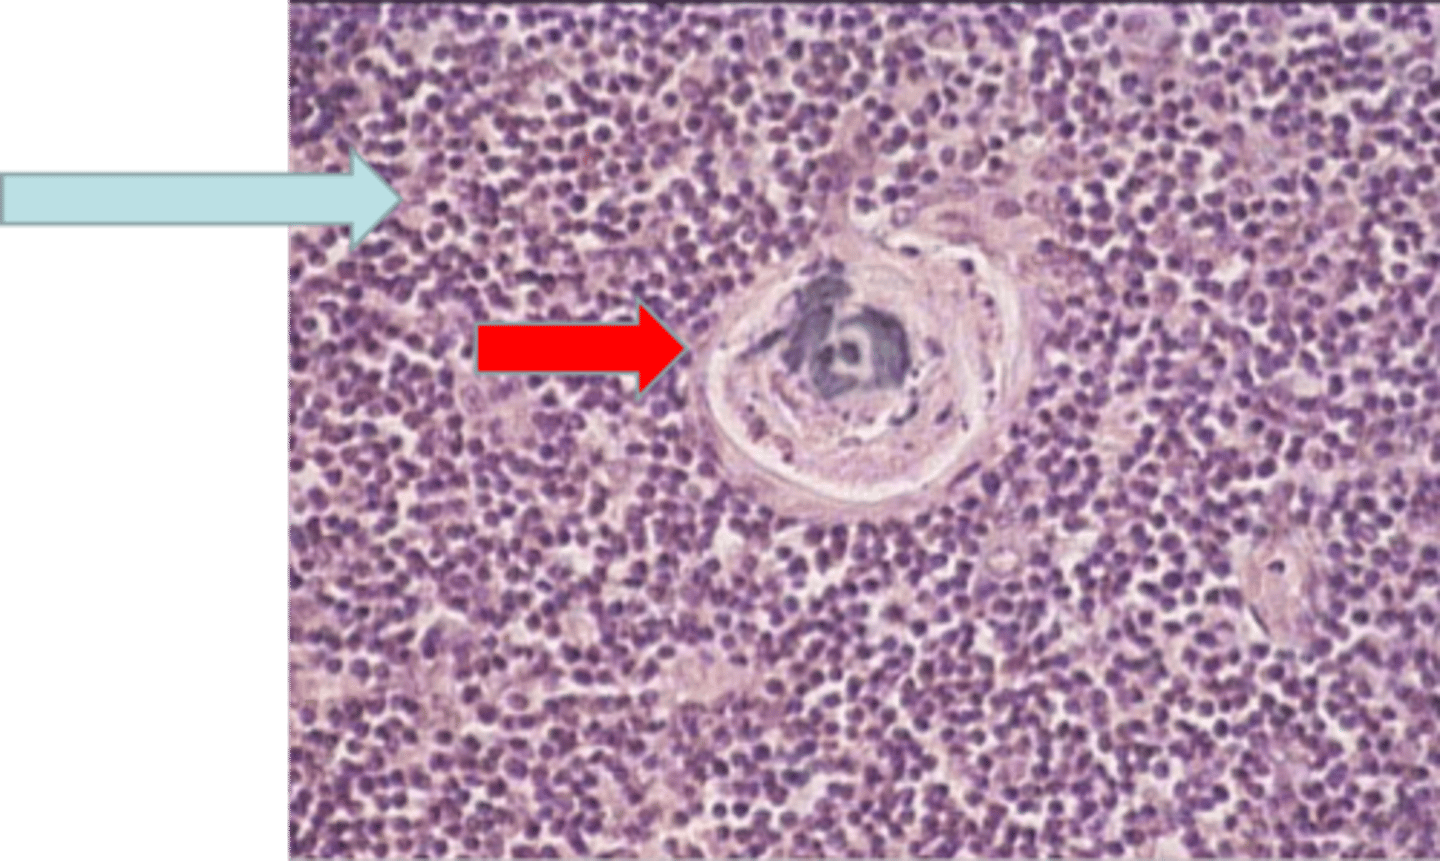

thymus

where is this tissue? thymus

yellow arrow

medulla containing T lymphocytes

blue arrow medulla containing T lymphocytes

Hassall's corpuscle

red arrow Hassall's corpuscle

Where is this tissue located? thymus

Thymus - Hassall´s corpuscle

blue arrow Thymus - Hassall´s corpuscle